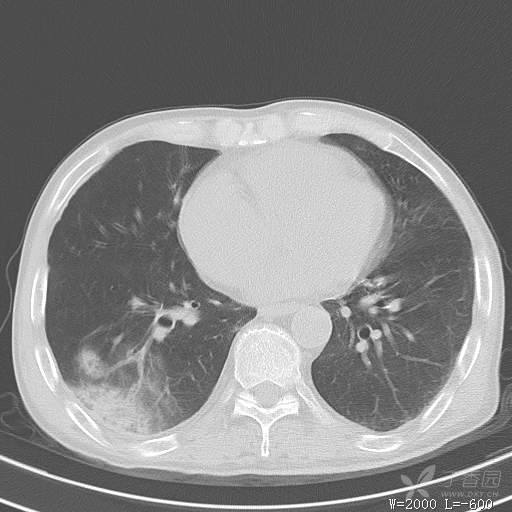

简要病史:主因发热伴腰背部疼痛2小时于2018-06-27,09:30 入院。患者无高血压,冠心病、糖尿病病史,无慢性咳喘史,不吸烟。否认食物药物过敏史。患者于入院前2小时出现发热,体温37.5℃,无咳嗽,咳痰,伴右侧腰背部疼痛,伴呕吐2次,呕吐物为黄绿色胆汁,大便2次,为稀便,无咯血,无胸闷、憋气,无鼻塞、流涕,无尿频、尿急、尿痛,就诊于我院,我院急诊查:上腹部CT:右肾结石,右下肺感染性疾病可考虑,血常规WBC13.54*109/L,GR%45.8%,急诊以“发热待查:肺感染?”收入院。

辅助检查:上腹部CT:右肾结石,右下肺感染性疾病可考虑,血常规:WBC13.54*109/L,GR%45.8%,。心肌酶示:谷草转氨酶12U/L,乳酸脱氢酶328U/L,肌酸激酶20U/L,肌酸激酶同工酶7U/L,α-羟丁酸脱氢酶277U/L,查凝血常规示:凝血酶原时间12.5秒,国际标准化比值1.07,活化部分凝血酶原时间32.6秒,纤维蛋白原浓度1.77g/L,凝血酶时间15.6秒。

临床诊断:1.腰背部疼痛原因待查:1.肺炎?2.泌尿系结石?。